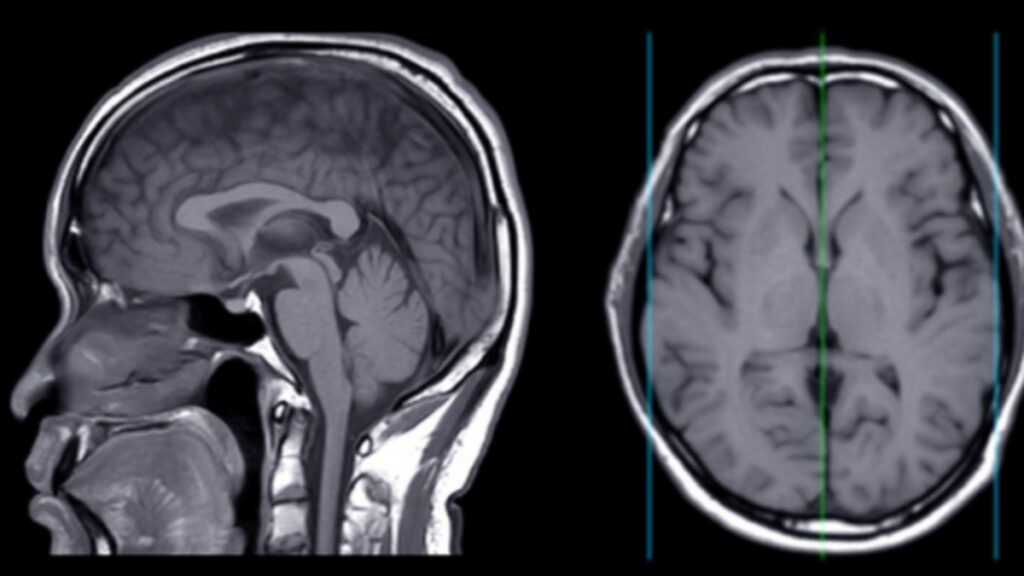

위버 박사의 새로운 이론은 발상의 전환을 요구한다. 그는 알츠하이머를 “뇌의 면역계 질환”으로 재정의한다. 베타-아밀로이드는 비정상적으로 생산된 독성 물질이 아니라, 뇌를 보호하기 위해 정상적으로 존재하는 면역 분자라는 것이다.

문제는 세균 막과 뇌세포 막의 지방 분자 구조가 놀랍도록 유사하다는 점이다. 뇌에 세균 침입이나 외상이 발생하면 베타-아밀로이드가 면역 반응의 일환으로 활성화되지만, 적과 아군을 구분하지 못해 자기 뇌세포까지 공격한다.

다만 전문가들은 신중한 접근을 당부한다. 뇌는 우주에서 가장 복잡한 구조로 알려져 있으며, 단일 원인론으로 설명하기 어렵다. 베타-아밀로이드 가설이 30년간 지배적이었던 것처럼, 새로운 이론도 충분한 검증이 필요하다는 지적이다.